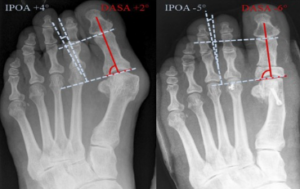

An Akin osteotomy is a surgical procedure performed on the foot, specifically on the big toe (the hallux). Unlike the more famous Scarf or Chevron osteotomies that cut and shift the metatarsal bone (the long bone in the foot), the Akin osteotomy is performed on the phalanx. More precisely, it is performed on the proximal phalanx of the hallux.

Think of it as straightening a crooked picture frame by adjusting the frame itself, rather than the hook on the wall. It is a powerful procedure for correcting a condition called hallux valgus interphalangeus, where the very tip of the toe points outward away from the body.

Because the code you choose must reflect where the work is being done. If the surgeon works on the metatarsal, you are in one family of codes. If they work on the phalanx (the toe bone), you are in another.